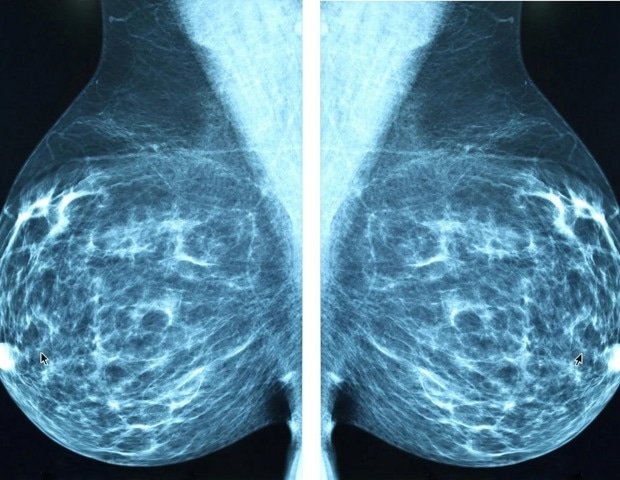

A new national survey reveals that many women aren’t sure when to start mammogram screening for breast cancer and think they should start later than doctors recommend.

The survey, commissioned by The Ohio State University Comprehensive Cancer Center–Arthur G. James Cancer Hospital and Richard J. Solove Research Institute (OSUCCC–James), found that 44% of women incorrectly believe that annual mammograms should begin at age 50. Leading medical organizations recommend that women at average risk for breast cancer start annual mammo40.

Confusion continues after the US Preventive Services Task Force (USPSTF) updated its mammogram recommendations in April 2024. The task force recommends average-risk women get a screening mammogram every other year starting at age 40. women, a guideline followed by OSUCCC – James.

In April 2026, the American College of Physicians updated its guidelines to recommend mammography for average-risk women ages 50 to 74 be performed every two years, citing individualized decision-making. OSUCCC – James follows guidelines that focus on radiology and recommend annual mammograms starting at age 40. Under the Affordable Care Act, annual screening mammograms starting at age 40 are covered by Medicare and most commercial insurance providers. Insurance coverage may vary. Patients should contact their insurance provider regarding specific coverage.